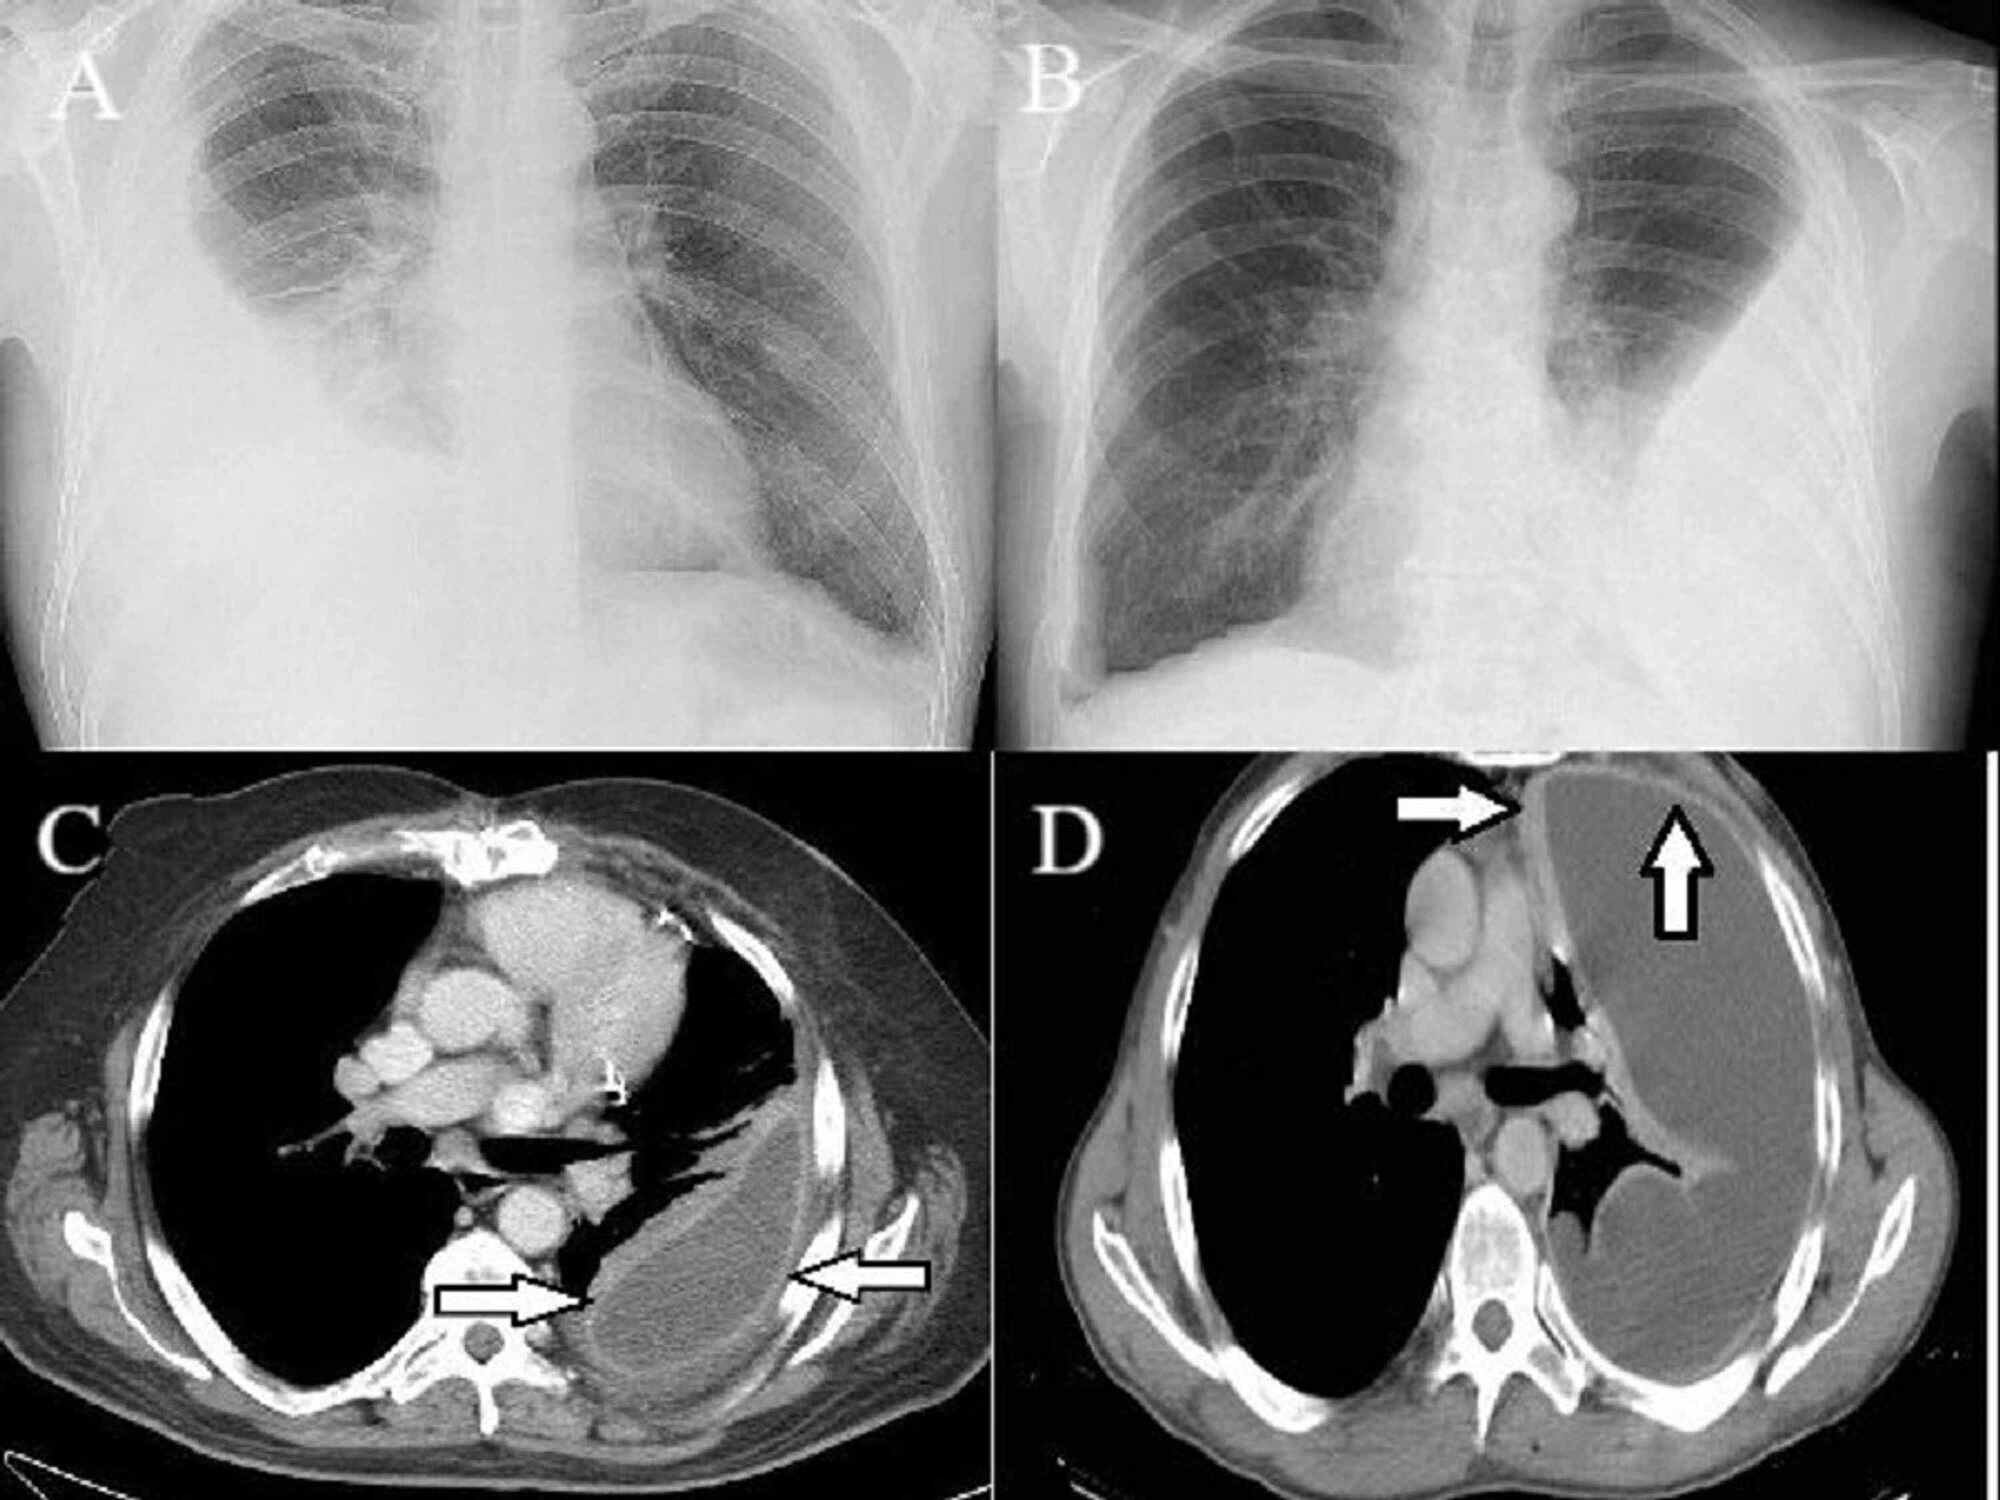

Decortication is a surgical procedure that removes a restrictive layer of fibrous tissue overlying the lung, chest wall, and diaphragm. The aim of decortication is to remove this layer and allow the lung to reexpand. When the peel is removed, compliance in the chest wall returns, the lung is able to expand and deflate, and patient symptoms improve rapidly.